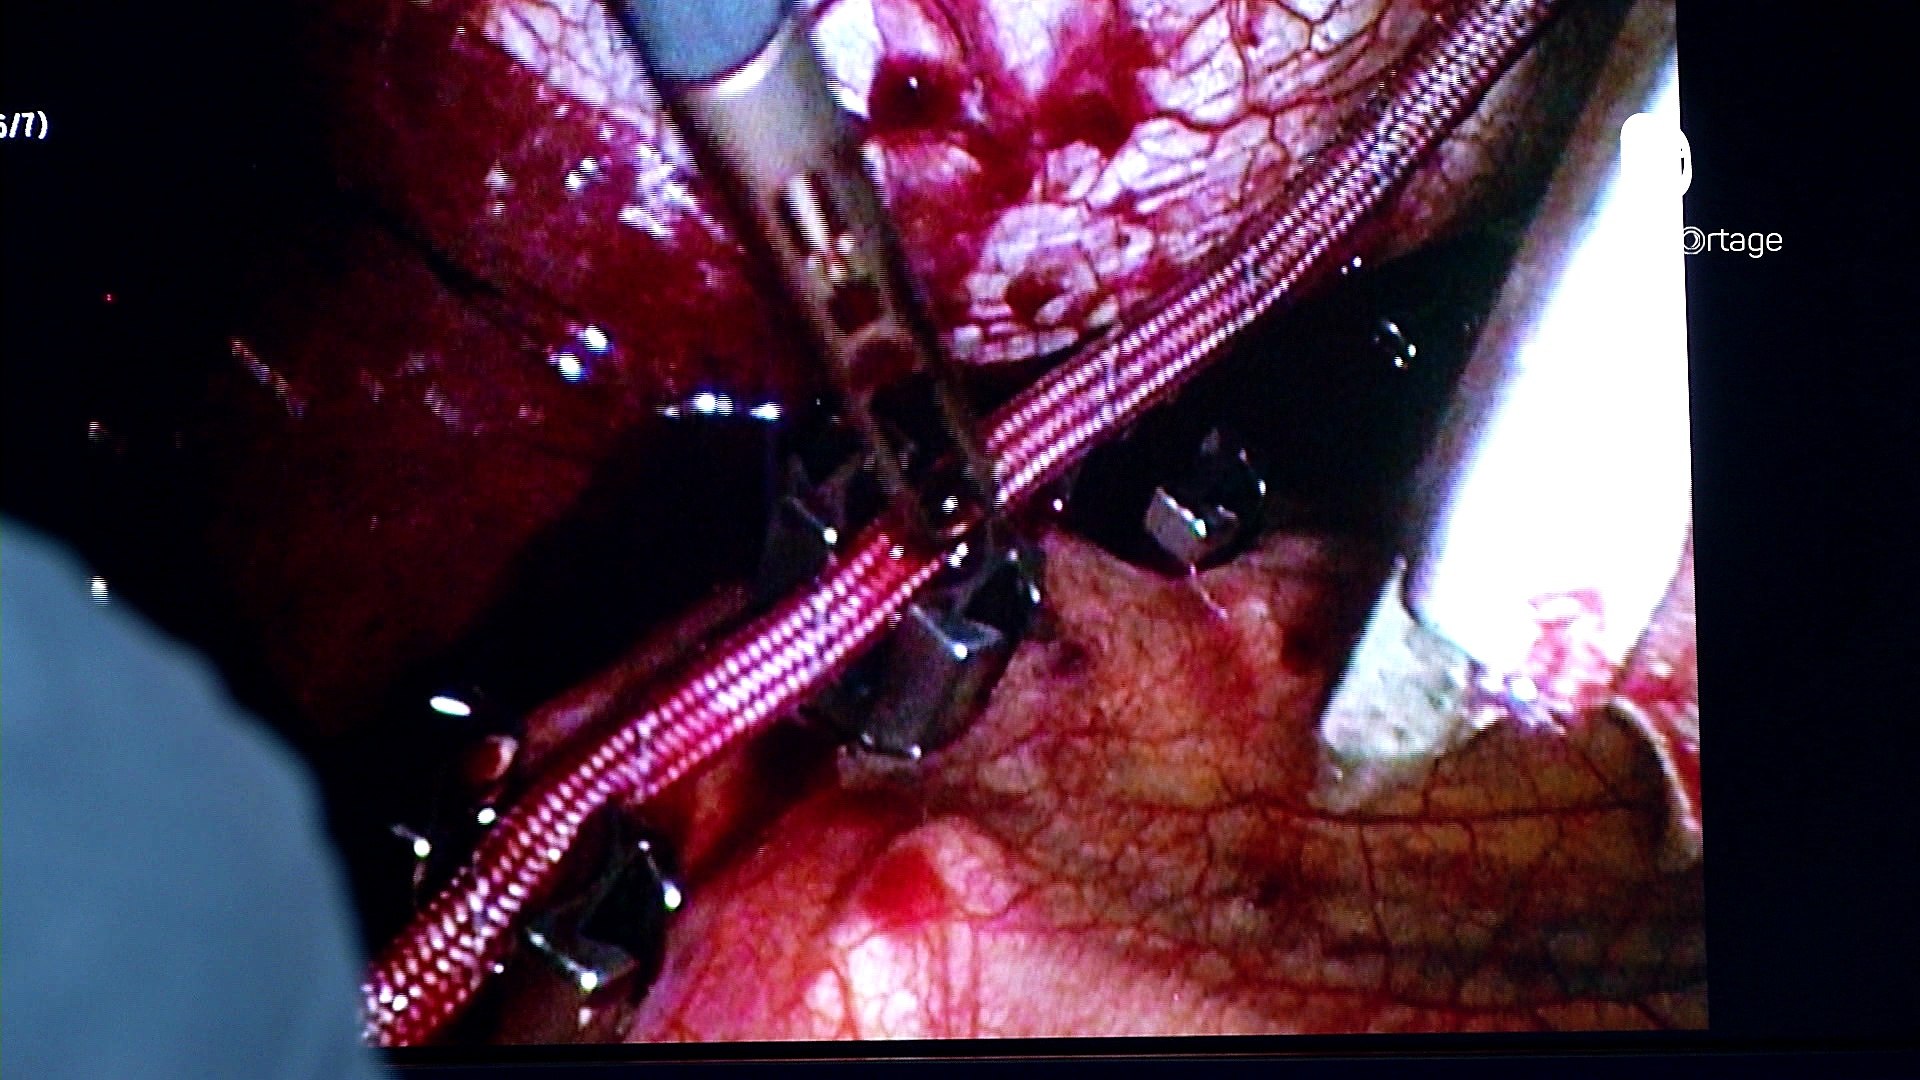

Reportage - Opération de la scoliose - Vidéo Dailymotion